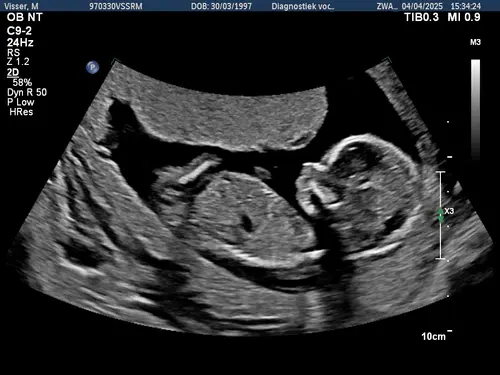

Hier is geen nub uit te halen of wel? Ik zit door al mijn foto's te kijken van de 13 weken echo maar ik kan niet echt een nub vinden, maar dat kan ook mijn eigen incompetentie hierin zijn hahaha

Nee hier zit het been voor. Als je er meer hebt kan je ze plaatsen ☺️